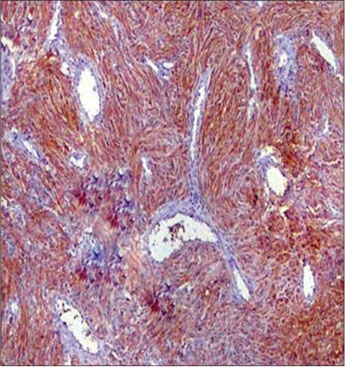

A total of 90 mesenchymal tumors of the GIT and pancreas diagnosed in SKIMS from January 2010 to December 2016 were reclassified on the basis of morphologic features and IHC into 77 (85.6%) cases of GIST and the remaining 13 (14.4%) cases as other mesenchymal tumors. The mesenchymal tumors included five cases of inflammatory myofibroblastic tumors, two cases of leiomyoma, four cases were sarcomas, one case was poorly differentiated carcinoma, and one was desmoid tumor. C-KIT positivity was seen in 72 (93.5%) cases and DOG 1 was positive in 77 (100%) cases [Figures 1], [2], [3], [4]. However, the correlation between DOG1 and CKIT was found to be statistically insignificant (P = 0.23). There was no significant association between DOG 1 expression and various histopathological parameters in the studied cases. Clinicopathological variables have been enumerated in [Table 1].

| Figure 3 CKIT staining

≥40 |